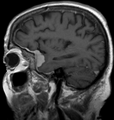

Dural tail sign, abbreviated DTS, is a finding in neuroradiology associated with meningioma,[1] but also described in other tumours.[2]

It is seen on MRI T1 images as a thickening with enhancement adjacent to a (mass) lesion.[2]